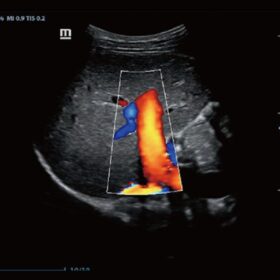

Ultrasound Mindray Z60 – Image Gallery